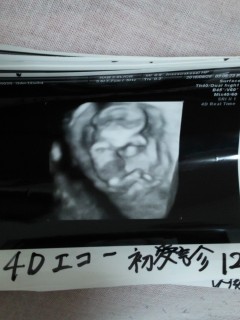

初めての4Dエコーは手でお顔を隠しておられました笑こんなことも出来るようになったんだと感動!大きさは6.5センチ。沢山動いてた~。先生も、すっごい動いてるなぁと思わず言ってくれました!

12週の4Dエコー写真です。前回より人間らしくなって、うるっとしました。12週でこんなに人間らしいなんて~ 次で性別がわかるといいなぁ(o^^o)エコー写真にほれぼれです(^-^)